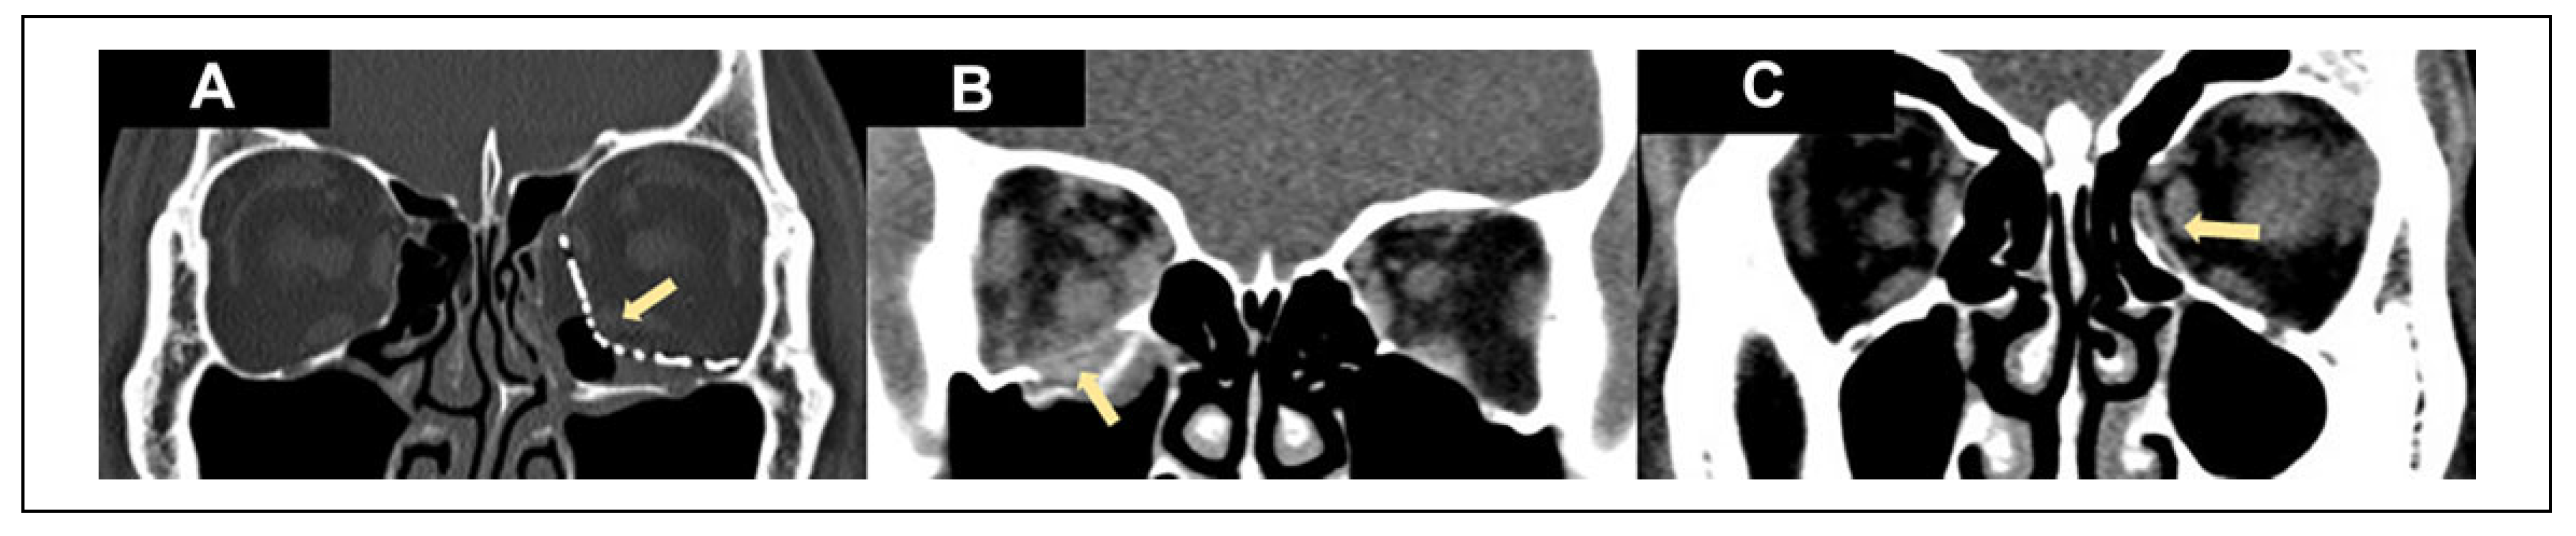

Figure 2. Various types of implants used for different types of fractures: Prefabricated anatomical titanium orbital implant for left combined floor and medial wall fracture (A); bioresorbable implant for right orbital floor blowout fracture (B); bioresorbable implant for left orbital medial wall blowout fracture (C). The arrows point to the implants.

Table 3 illustrates the type of fracture and type of implant used (Figure 2). When comparing the different types of fractures and the types of implants used, there was a significant difference in the types of implants used depending on the type of fracture (P < 0.001). In addition, after the Bonferroni correction was applied for comparison across multiple groups, bioresorbables, titanium plate, and porous polyethylene were used significantly more than titanium mesh for simple fractures. Porous polyethylene was used significantly more than prefabricated titanium plate. For complex fractures, titanium mesh implants were used significantly more than bioresorbables, titanium plate, and porous polyethylene. In addition, for complex fracture, prefabricated titanium plate was used significantly more than porous polyethylene.

In contrast, prefabricated anatomic titanium orbital implants were used significantly more than other implants for complex fractures (Figure 2A). This is likely related to anodized titanium implants’ long track record in craniofacial reconstruction. It has the following advantages: easy to use, has stood the test of time, possesses good mechanical strength, has rigid fixation, and is well-seen on imaging.[30,31] Titanium mesh has demonstrated excellent biocompatibility and provides long-lasting stability of the internal orbital reconstruction.[32] Although titanium mesh is easily manipulated intraoperatively, the complex internal orbital shape required is often difficult to accurately recreate. Fortunately, despite its complexity, the orbital shape varies only a small amount between individuals and commercially available preformed anatomic orbital implants have been developed to streamline this process.[33,34] The latter hence allows the distinct orbital anatomical contours to be addressed, particularly the orbital strut between the medial wall and floor, and the S-shaped bulge of the posterior orbit which is often ill addressed by sheet implants.

Simple orbital fractures were the most common type of fractures in our series. For simple fractures, we found that bioresorbable (Figure 2B), porous polyethylene (Medpor) and titanium plate implants were used significantly more than titanium meshes. The amount of empirical support for individual materials used for orbital floor fracture reconstruction differs and no definite conclusion has been reached regarding the best material for orbital floor fracture repair. There is a lack of standardized guideline or consensus with different surgeons having different preferences and practices that are each supported by varying amounts of research.[7,26] Both bioresorbable and porous polyethylene (Medpor) implants have been shown to be stable, biocompatible, easily shaped two-dimensionally and allow tissue incorporation, with no additional donor site required.[22,23,24,25,27,28,29] These properties make them easy to use and suitable for simple 1-walled small to medium and large sized blowout fractures.[29] The degradable nature of bioresorbable implants also make them an attractive option for simple blowout fractures, providing enough mechanical strength during the initial bone healing process while eventually hydrolyzed, hence avoiding all the potential longterm complications of permanent implants.